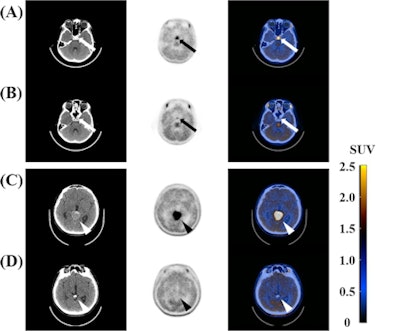

Clinical characteristics, imaging findings, and tumor markers such as α-fetoprotein (AFP) and beta-human chorionic gonadotropin (HCG) in serum and cerebrospinal fluid were used as clinical variables. Maximum standardized uptake value (SUVmax), tumor-to-normal tissue (T/N) ratio, and visual scoring of tumor were used as C-11 MET-PET/CT parameters.

All of the intracranial germinomas were well visualized on C-11 MET-PET/CT and the SUVmax of intracranial germinomas was higher than that of intracranial nongerminomas (p = 0.005), according to the findings.